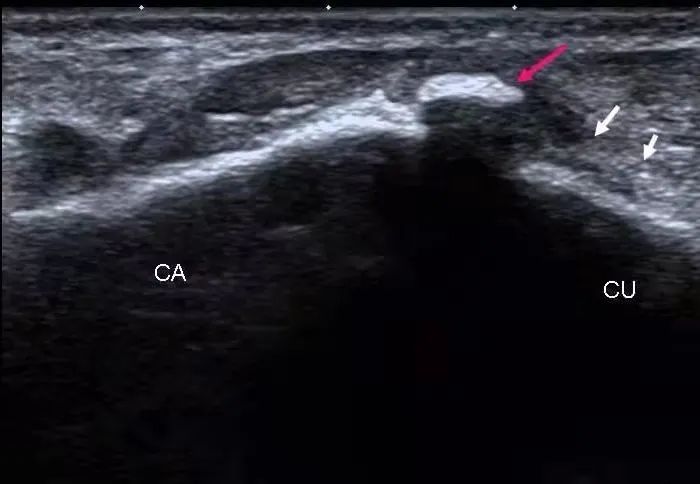

肌骨彩超提示:右侧颈7横突与颈肋相连,右侧臂丛神经下干受压。

红线描绘出肿胀受压的臂丛下干

超声显示:尺神经于肘管近端及远端增粗,符合肘管综合征(尺骨骨赘形成,压迫尺神经)